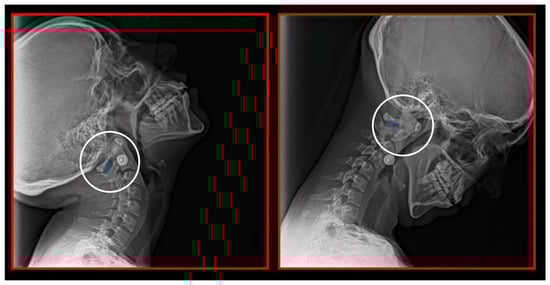

7.3. Ponticulus Posticus Syndrome

10.1. Neck X-ray

10.2. Computed Tomography of Cervical Spine